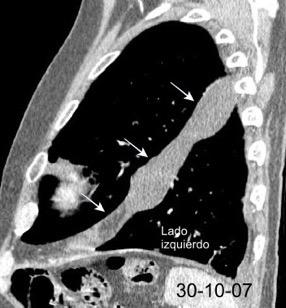

Marzo 2014: Perforación longitudinal distal secundaria a episodio de vómito (síndrome de Boerhaave). Derrame pleural izdo. que evoluciona a empiema.

Wang C-T et al. Tension hydropneumothorax in a Boerhaave syndrome patient: A case report . World J Emerg Med, 2021. Katabathina V et al. Nonvascular, nontraumatic mediastinal emergencies in adults:a comprehensive review of imaging findings. Radiographics. 2011.